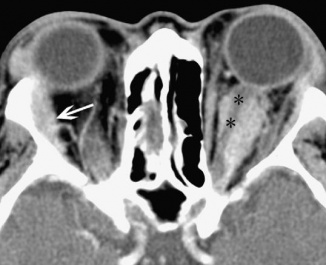

Imaging will demonstrate nonspecific thickening of structures. Blurring of the scleral margin may be seen (Figure 5).

Figure 5: CT image showing thickening and blurring of left eye uveoscleral (asterisks). (Courtesy of Z.X. Ding).